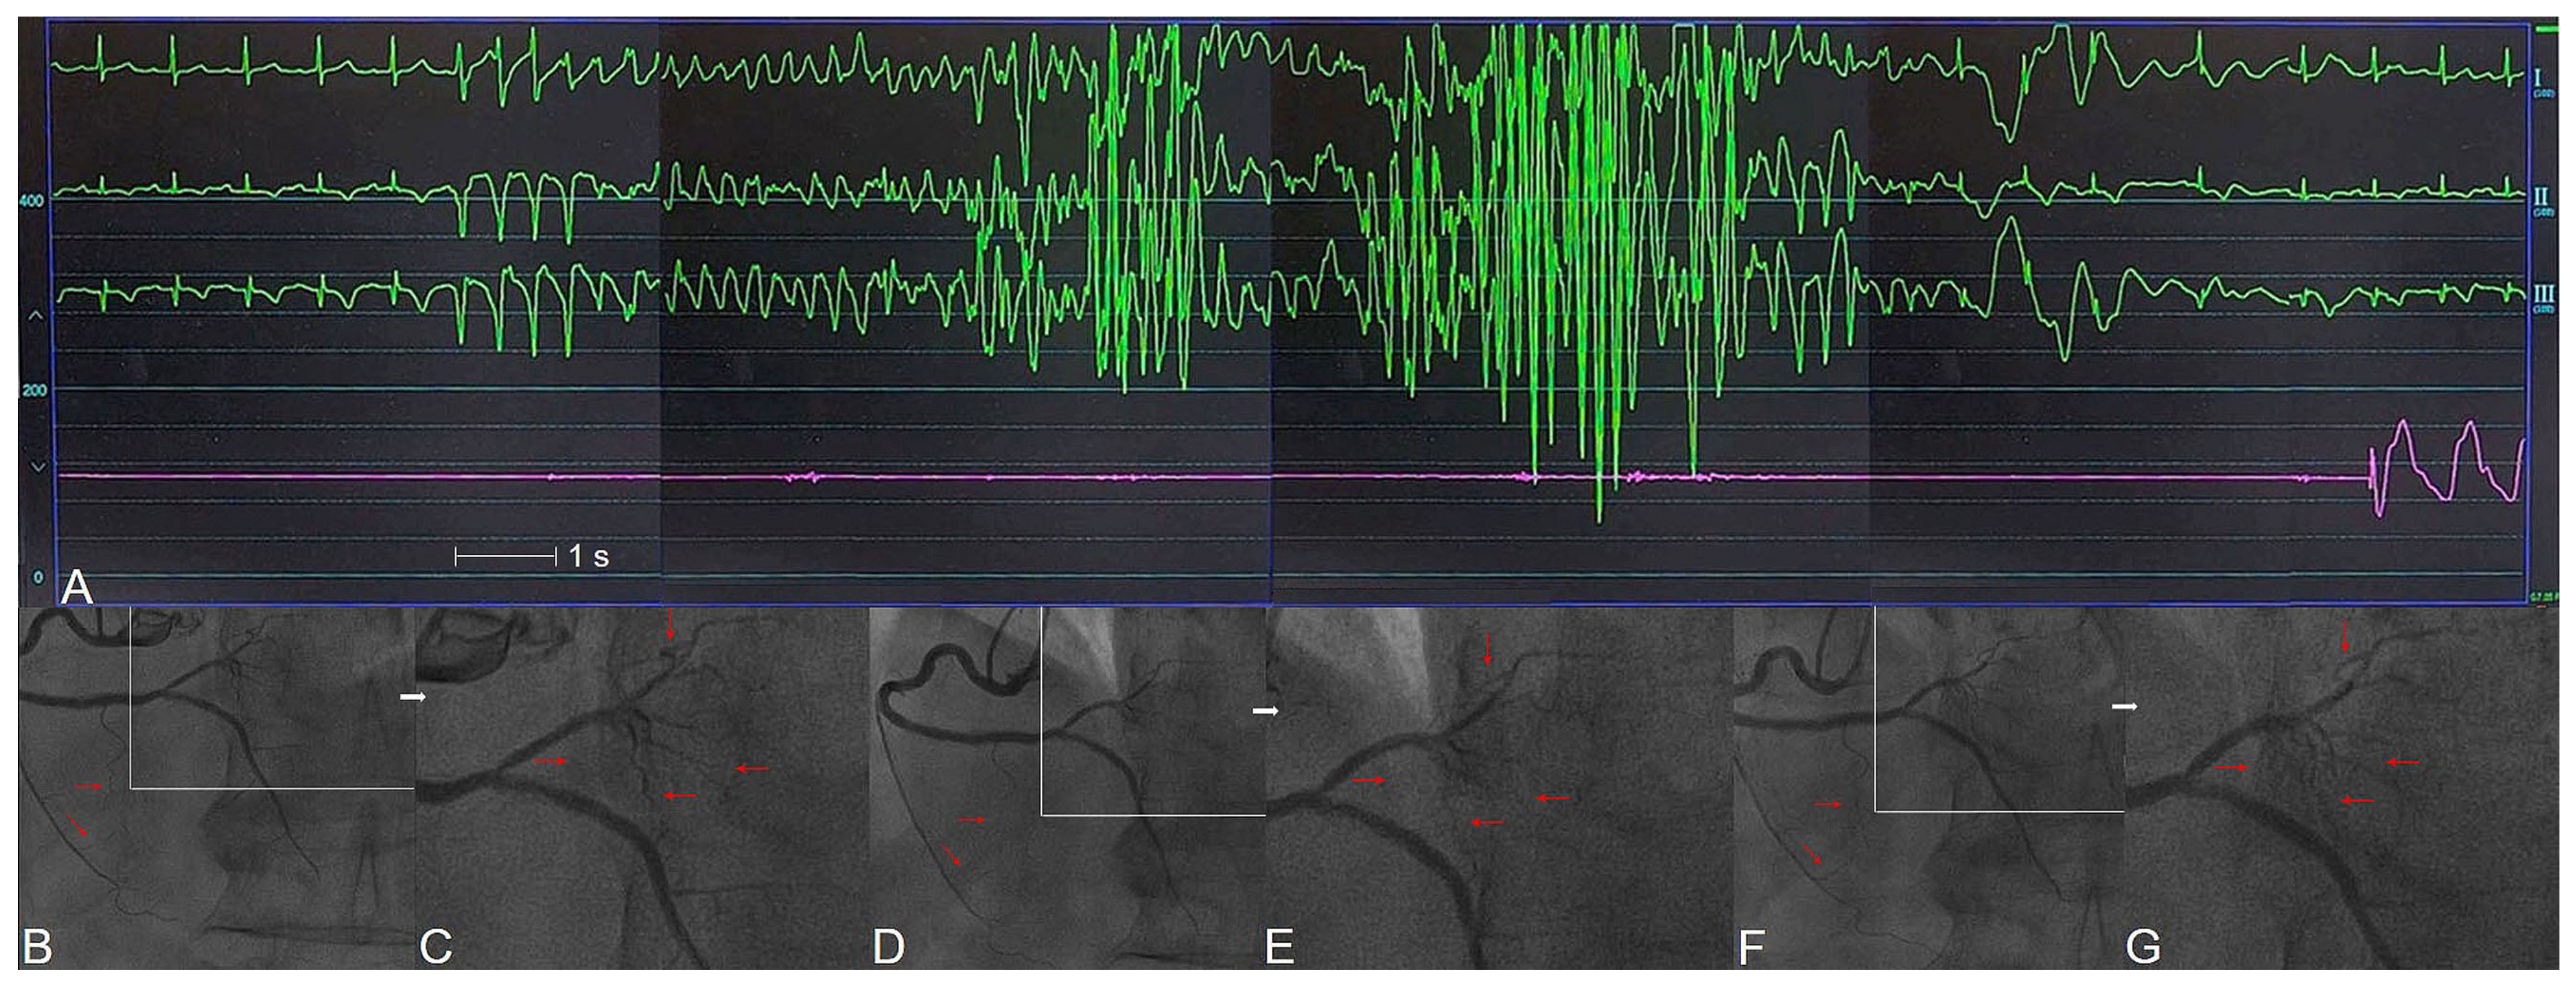

- Hung, M.J.; Cheng, C.W.; Yang, N.I.; Hung, M.Y.; Cherng, W.J. Coronary vasospasm-induced acute coronary syndrome complicated by life-threatening cardiac arrhythmias in patients without hemodynamically significant coronary artery disease. Int. J. Cardiol. 2007, 117, 37–44. [Google Scholar] [CrossRef] [PubMed]